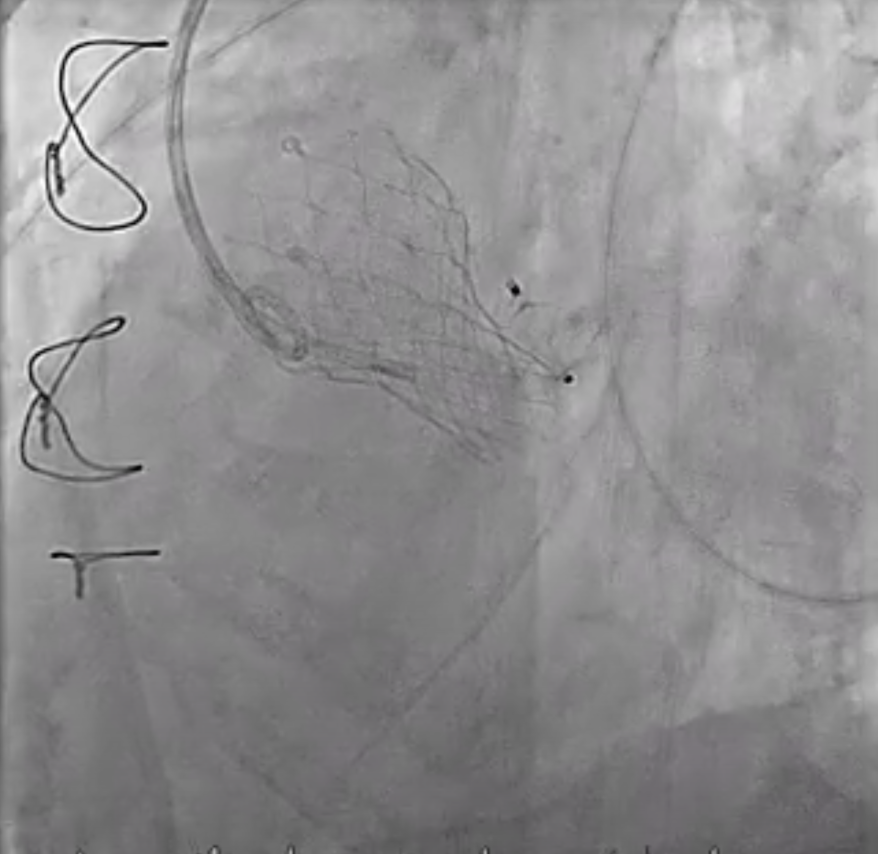

Under local anesthesia, the RFA was punctured, and a 6-Fr sheath was introduced. A 6-Fr pigtail catheter over a 0.035-inch J-tip wire was advanced into the ascending aorta, and an aortogram demonstrated a moderate PVL originating from the surgical valve ring and the aortomitral curtain.The pigtail catheter was replaced with a 6-Fr MPA2 catheter to delineate the anatomy of the transcatheter heart valves and PVL. A 6-Fr JL 3.5 catheter was then used for a nonselective left coronary angiogram, confirming the PVL adjacent to the aortic annulus. A Terumo guidewire was advanced through an Amplatz Left (AL1) catheter and successfully crossed the PVL into the left ventricle (LV).For device delivery, the LFA was also punctured, and a 6-Fr sheath was inserted. A pigtail catheter was placed in the ascending aorta to identify the left main ostium. Attempts to advance an AGA Amplatzer Vascular Plug (AVP) 10/7 mm through the PVL were made using multiple guiding systems, including AL and JR4 catheters, a 6-Fr Shuttle sheath, and a Superstiff 0.035-inch wire, but initial passage into the LV was unsuccessful.Balloon sizing was performed using a Boston Scientific Mustang balloon (4.0 mm ¡¿ 20 mm ¡¿ 75 cm) inflated to 4 atm. The 6-Fr sheath was exchanged for a 7-Fr sheath, and a 7-Fr Boston MP 90-cm guiding catheter was advanced into the LV. An AGA Amplatzer Vascular Plug 10/7 mm was successfully deployed across the PVL. Final aortography confirmed successful occlusion of the PVL.

Final (5_17 angio).mp4